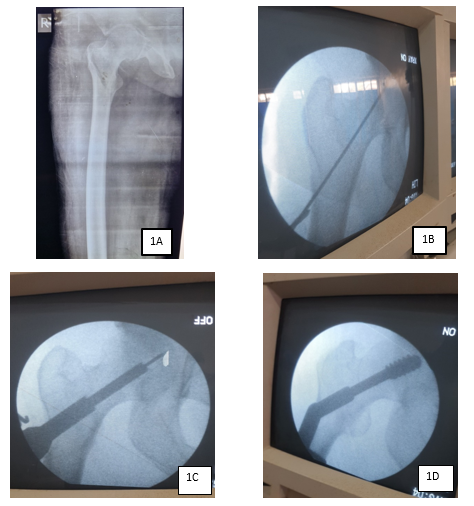

At the immediate postoperative period, graded weight-bearing was allowed as pain was tolerated. Patients were followed up after the average 5 days of the postoperative period at 6 weeks, 12 weeks, 6 months and 1 year in the outpatient clinic. During the follow-up times, anteroposterior and lateral view radiographs of the operated areas were taken, and findings including any associated complications were noted (Figure 3). Additionally, functional outcomes were assessed and Parker's mobility scores were recorded (12). This score was assessed in all our patients both preoperatively and postoperatively and takes into account the patient’s ability to independently walk with a maximum score of 9 to the lower score with needs for support and lowest score of 0 in completely non-ambulant patients.

Figure 3 The same patient in figure 1 presented with a healed fracture at 1 year follow-up.